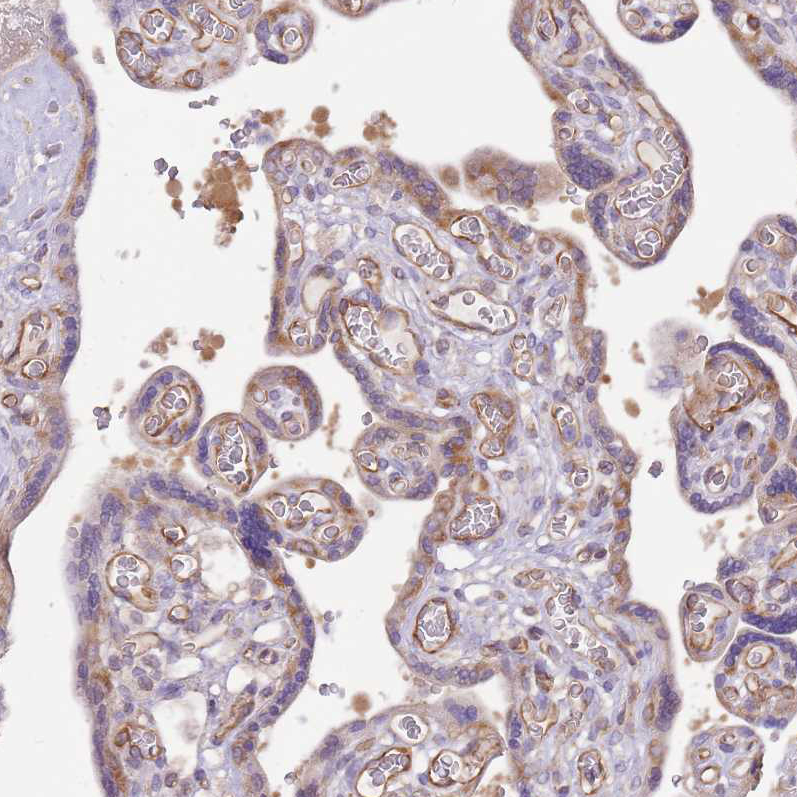

Immunohistochemical staining of human placenta shows weak to moderate cytoplasmic positivity in trophoblastic cells.